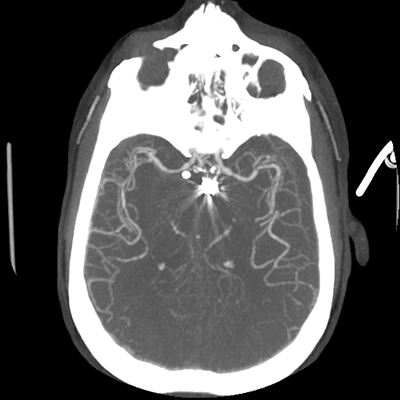

CTA head (MIP)

Starting with the non-contrast head CT, we can appreciate that there's actually not much residual subarachnoid blood at all; it's essentially all resorbed already (and cleared through the EVD). The ventricular caliber is stable. With the CTA head (for convenience's sake, the MIPs were shown), it's subtle, but we can see that the PCAs on each side are not as smooth and regular. The right MCA, starting at the bifurcation, also becomes narrower. This is [radiographic] vasospasm. Now, looking at the CT perfusion-- specifically, the Tmax (MTT) map that were selected-- there's clearly some abnormality within the bilateral cerebellar hemispheres and occipital lobes. Not a lot, but it's there. Delving further into this map, we can appreciate that the areas of abnormality are mainly green, signifying that these areas have Tmax > 6 seconds. This is the threshold that is specific, not sensitive, for vasospasm.

Putting this all together, we have thus identified radiographic vasospasm with the vessel imaging, with perfusion abnormalities that are concordant with it. Does the area of vasospasm and hypoperfusion correlate with the patient's clinical exam?